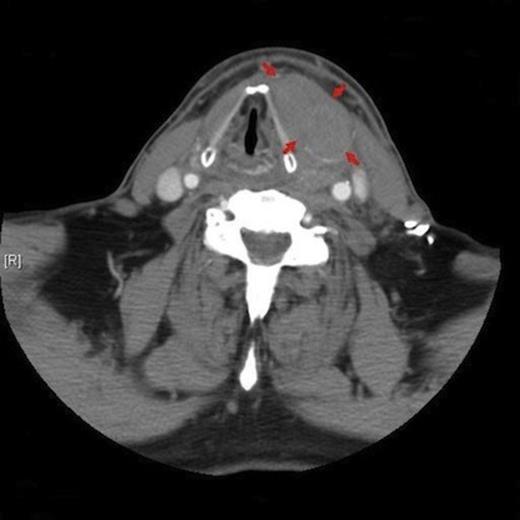

His airway was patent and no breathing difficulties were noted. Admission blood tests revealed an INR of 2.6 and haemoglobin of 13.5g/dl. Flexible nasendoscopy demonstrated swelling and bruising of the left aryepiglottic fold and vocal cord; which were hypomobile in comparison to the uninvolved right cord. Computerised tomography (CT) was undertaken on admission and magnetic resonance images (MRI) obtained the next day. A 5×4cm homogenous hypodense mass was visible lying separate and just lateral to the left thyroid lobe; deep to the left strap muscles and anterior to sternocleidomastoid (Figure.2).

Axial CT image demonstrating the left anterior cervical mass (outlined with arrows) and associated contralateral shift of the adjacent airway.